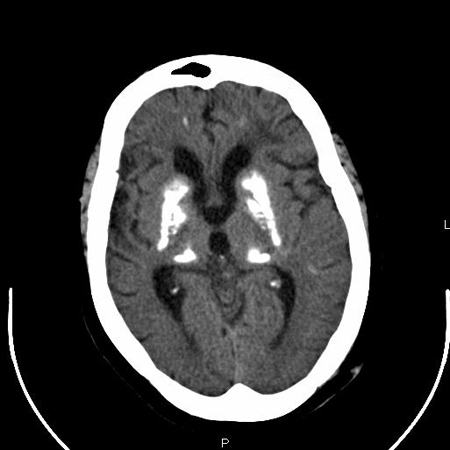

Hand radiograph suggestive of shortened IV and V metacarpals

From the collection of Kent Wehmeier, University of Florida Jacksonville